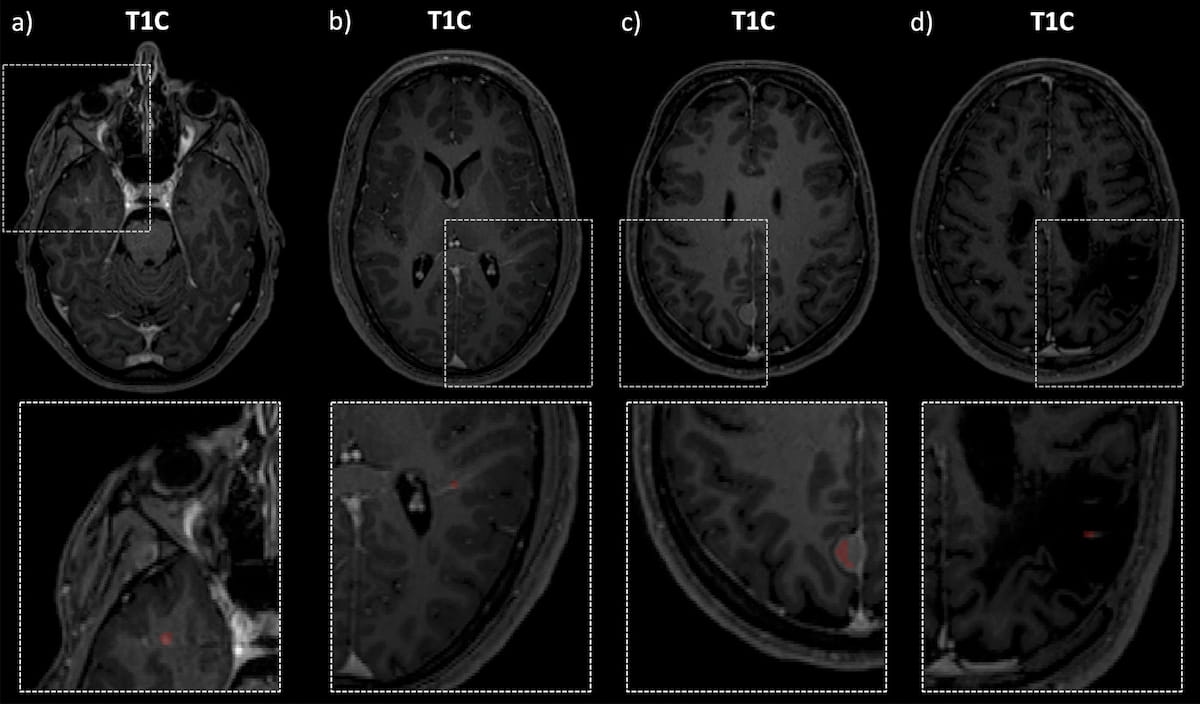

While contrast-enhancing (CE) lesions on brain magnetic resonance imaging (MRI) play a key role in the management of patients with multiple sclerosis (MS), significant variation in the morphology of CE lesions and the time-consuming nature of manual segmentation of these lesions can lead to errors by radiologists. However, an emerging convolutional neural network (CNN) may facilitate optimal diagnosis and segmentation of lesions in this patient population.

The researchers noted that the majority of false negative lesions with the CNN model had punctual enhancement in comparison to the prevalent ring enhancement seen with true positive lesion assessments. False negative lesions often occurred in an infratentorial location, were smaller in size and occurred more at lower contrast, according to Hedderich and colleagues.